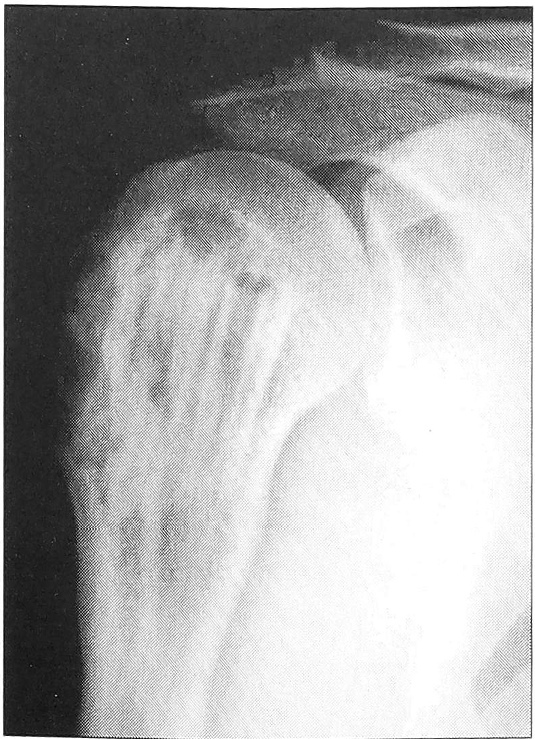

Анализ рентгенограмм показал, что через 1 мес после хирургических вмешательств картина неоднородной «глыбчатой» структуры в местах заполнения дефектов «Остеоматриксом» или в пространствах между его гранулами и аллоимплантатами, выявлявшаяся сразу после операции, полностью исчезала. Рентгеновская тень была практически однородной и имела умеренную плотность (рис. 1). Через 3 мес в большинстве случаев (66%), а через 6 мес у всех больных места, куда помещался «Остеоматрикс», по плотности рентгеновского изображения были неотличимы от окружающей губчатой костной ткани (рис. 2). Признаки перестройки замороженных кортикальных аллоимплантатов, применявшихся совместно с гранулами «Остеоматрикса», во все сроки наблюдения были минимальными (рис. 3), тогда как поверхностно-деминерализованные кортикальные аллотрансплантаты к 6-му месяцу частично инкорпорировались в материнское костное ложе (рис. 4).

Рис. 3. Рентгенограмма больной Б. 21 года. Диагноз: рецидив гигантоклеточной опухоли плечевой кости. Через 9 мес после операции с пластикой дефекта «Остеоматриксом» в сочетании с замороженными кортикальными аллоимплантатами.

Рис. 5. Рентгенограммы больной К. 51 года. Диагноз: хондрома III пястной кости.а — до операции; б — после операции с пластикой дефекта «Остеоматриксом»; в — через 1 мес; г — через 5 мес.